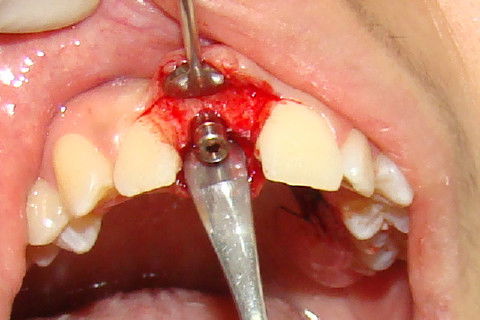

Vista da depressão gingival vestibular na região do implante a ser reaberto

Exposição do implante, colocação de cicatrizador, antes da colocação do enxerto

Colocação do enxerto gengival